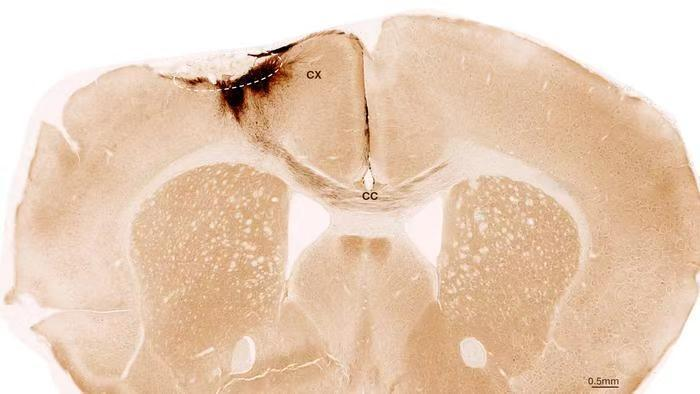

神经干细胞移植后小鼠大脑的冠状切面。虚线圆圈标示了中风区域。移植的人类细胞所发出的神经突起被染成深棕色。这些神经突起不仅向局部皮层(CX)延伸,还通过胼胝体(CC)延伸至另一侧大脑半球。图片来源:苏黎世大学

此次,团队采用来源于人类诱导多能干细胞的神经干细胞,这类干细胞可由普通体细胞重编程获得,具备分化为多种神经系统细胞的能力。为模拟人类中风,他们在小鼠脑内诱发了与人类高度相似的永久性脑损伤。这些小鼠经过基因改造,不会排斥移植的人类细胞。在中风发生一周后,团队将神经干细胞精准移植到受损脑区,并利用多种成像与生化技术对后续变化进行了长达5周的追踪。

结果显示,移植的干细胞在受损脑区内成功存活,其中大部分分化为成熟的神经元,并与宿主原有的神经网络建立了功能性连接,实现了电信号的传递。这表明新生成的神经元真正融入了大脑的运作体系。